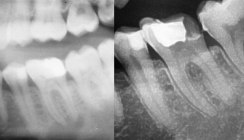

In einem zweiten Termin haben wir die Behandlung des Zahnes 44 weitergeführt. Nach erneuter sehr vorsichtiger Sondierung und NaOCl-Spülung wurde mit einem Apex-Locator die Arbeitslänge elektrometrisch bestimmt. Auch am Zahn 44 betrug diese 21 Millimeter. Nach der manuellen Aufbereitung und Reinigung bis ISO 25/.02 haben wir mit dem RECIPROC-System nachbereitet. In einem dritten Termin konnten beide Kanalsysteme nach bereits eingetretener Beschwerdefreiheit mit einer Kombination von kalter und warmer Obturationstechnik mit Guttapercha abgefüllt werden. Wie auf der radiologischen Kontrollaufnahme der Wurzelfüllung des Zahnes 44 zu erkennen ist (Abb. 5), besteht das Hauptrisiko bei s-förmig geschwungenen Wurzelkanalsystemen in einer Begradigung des Kanalverlaufs.

Um eine iatrogene Schwächung der Kanalwände oder gar Strip-Perforationen der Innenkurvatur zu vermeiden, sollte auf eine Aufbereitung des Kanalsystems über ISO 25 verzichtet werden. Gerade maschinelle Aufbereitungssysteme bergen aufgrund der sehr starken Schneidleistung der Feilen ein hohes Risiko der Begradigung. Dies auch vor dem Hintergrund, dass diese Feilen zumeist eine sehr große Konizität (Taper) von bis zu .08 aufweisen.